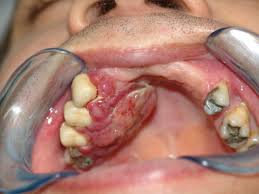

De acordo com ele, como o tratamento contra o câncer provoca a queda da imunidade, uma situação que seria corriqueira em uma pessoa saudável pode sair do controle no caso do paciente oncológico. Roger explica que o problema é que a quimioterapia não é seletiva e, além de atacar as células do tumor, também ataca células de outros tecidos, como os da boca. Por isso, diz ele, surgem as feridas, chamadas de mucosites.

Comuns em pacientes oncológicos, essas feridas bucais são porta de entrada para bactérias que levam a infecções possivelmente fatais ao organismo já debilitado. "O paciente, que já enfrenta uma debilidade por causa da doença, torna-se vulnerável a infecções por causa das feridas", esclarece Roger. "Isso sem falar da dor que impede que ele (paciente) coma certos alimentos e que beba água. Ele fica ainda mais debilitado."

No caso daqueles que fazem tratamento com radioterapia, além das mucosites há também o risco de desenvolver as chamadas cáries de radiação. Um dos fatores que levam a essas cáries é o efeito da radiação sobre a produção de saliva. "Sem a saliva, os dentes quebram mais facilmente e as cáries progridem rápido", explica Roger, que além de atuar no Icesp também é professor da Universidade Estadual de Campinas (Unicamp).